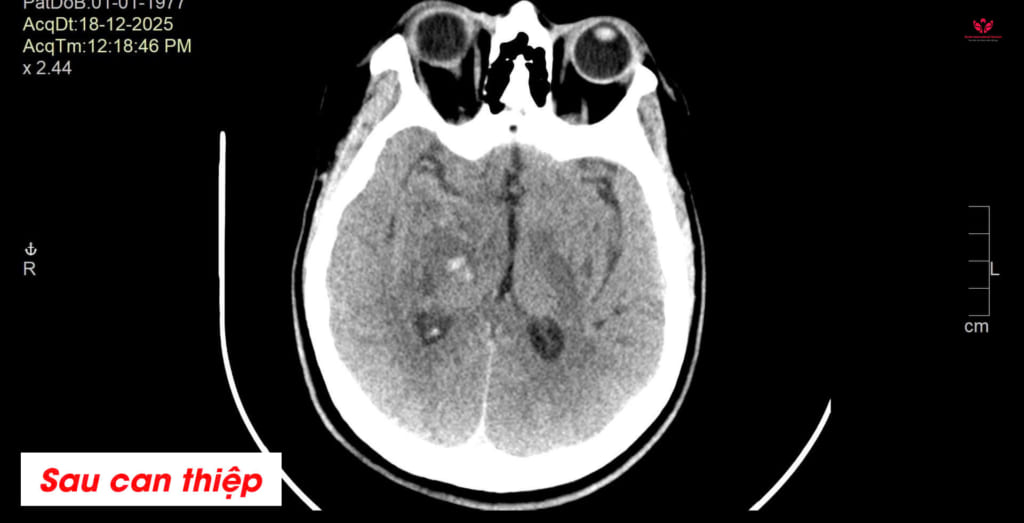

Sau phẫu thuật, chị T. được chuyển về khoa Hồi sức tích cực (ICU) để theo dõi sát. Kết quả CT não sau mổ cho thấy máu tụ đã được lấy sạch, tình trạng chèn ép não được cải thiện.